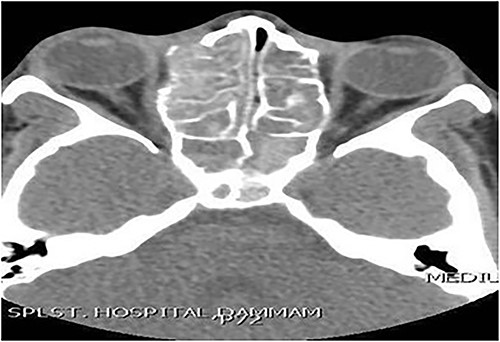

A 13-year-old male presented with progressive right-sided nasal obstruction followed by slowly progressive right eye proptosis noticed by parents for 1 year duration. CT scan of the paranasal sinuses (Fig. 2) confirmed the diagnosis of AFS. The child underwent FESS and received medical treatments post-operatively. The patient remained symptom-free for 4 years follow-up.

Axial CT paranasal sinuses shows the right ethmoid and sphenoid sinuses with complete obliteration and hyperdense (metallic) contents. It is associated with expansion of the ethmoid sinuses and lateral displacement of the right lamina papyracea causing right eye proptosis.